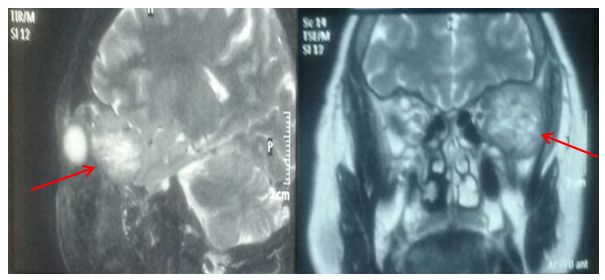

A magnetic resonance image (MRI) weighted in T2 was obtained at the National Institute of Neoplastic Diseases that showed left and anterior lateral displacement of the eyeball with alteration of the signal in the bones of the left temporal and orbit (Figure 1).